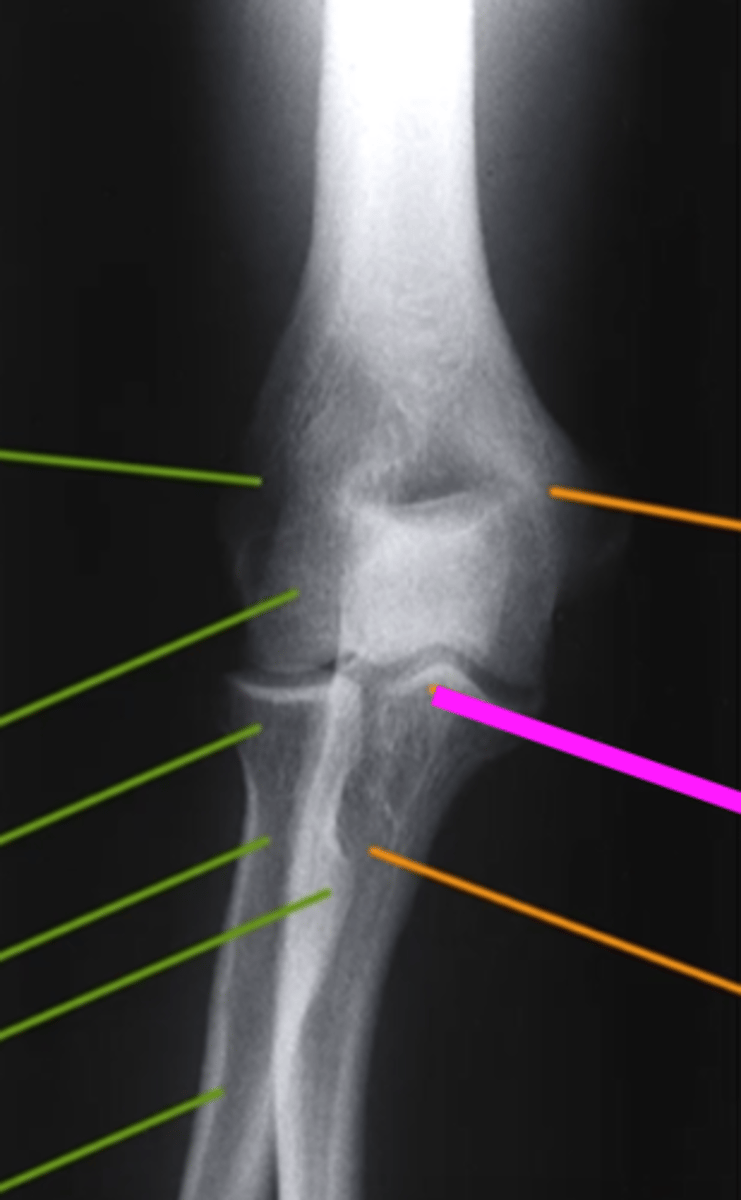

internal oblique elbow

what view is this

coronoid process

What does the blue line point to?

external oblique elbow

radial head

what does the green line point to?